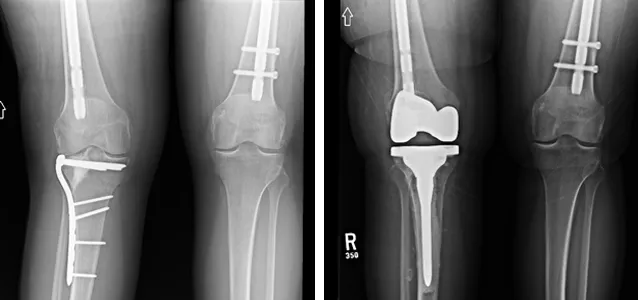

Figure 2: Knee X-rays illustrating a tibial plateau fracture.